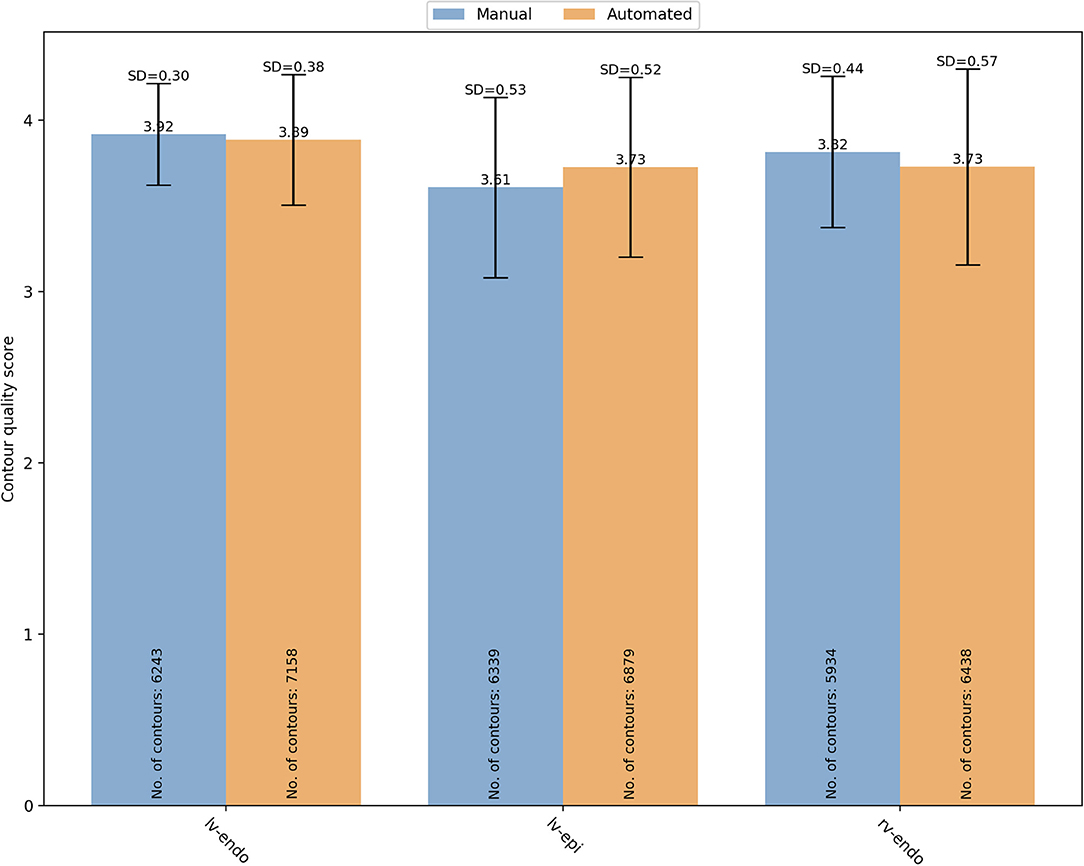

Firstly, we analyzed the distribution of quality scores between the two segmentation methods based on the contour type (Figure 5).

Figure 5. Overall mean quality scores for LV endocardial, LV epicardial and RV endocardial contours obtained from manual (blue) and automated (orange) segmentation. LV, left ventricle; RV, right ventricle; SD, standard deviation.

For manual segmentation, the mean quality scores by contour type were 3.92 ± 0.30 (n = 6,243), 3.61 ± 0.53 (n = 6,339), and 3.82 ± 0.44 (n = 5,934) for LV endocardial, LV epicardial, and RV endocardial contours, respectively. Compared to LV epicardial, both LV endocardial (OR (95% CI) = 22.89 (17.26–30.35) and RV endocardial (OR (95% CI) = 6.00 (4.74–7.58) had significantly higher quality (p < 0.0001). For automated segmentation, instead, the mean quality scores were 3.89 ± 0.38 (n = 7,158), 3.73 ± 0.52 (n = 6,879), and 3.73 ± 0.57 (n = 6,438) for LV endocardial, LV epicardial, and RV endocardial contours, respectively. Compared to LV epicardial, both LV endocardial (OR (95% CI) = 9.84 (7.09–13.66) and RV endocardial (OR (95% CI) = 1.68 (1.27–2.22) had significantly higher quality (p < 0.0001). A significant interaction was found suggesting that the differences in quality between contour types was more pronounced for the manual scores.